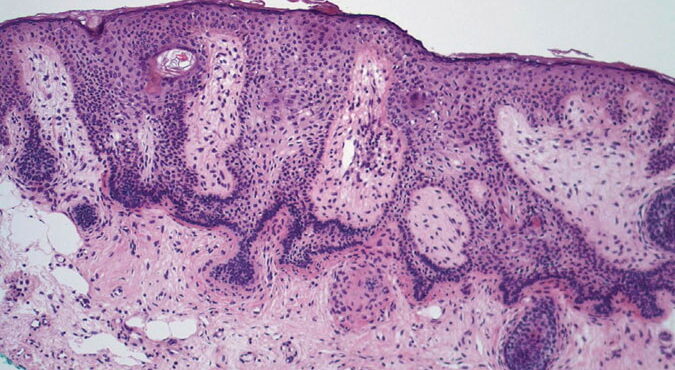

Read MoreForeign body reaction = ارتكاس للجسم الاجنبي Foreign Body Reactions Foreign substances, when injected or implanted accidentally into the skin, can produce a nonallergic foreign-body reaction or, in persons specifically sensitized to them, an allergic response (. In addition, certain substances formed within the body may produce a nonallergic foreign-body reaction when deposited in the […]